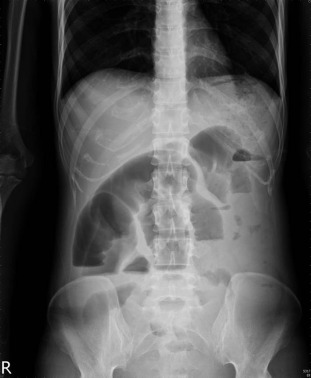

Baseline blood examinations revealed: hemoglobin 9.0 g/dL, white blood cell count 6200/mm3 , protein 3.0 g/dL, albumin 1.1 g/dL, total cholesterol 91 mg/dL, and normal renal and liver biochemistry. Plain abdominal film showed segmental dilatation of jejunal loops and intestinal obstruction was considered (Figure 1 ). A barium meal study disclosed marked dilatation of the segmental ileal bowel loops with air-fluid level and suggestion of mechanical obstruction (Figure 2 ). Abdominal computed tomography (CT) demonstrated significant dilatation of the distal jejunum to the proximal ileum, with a suspicious thickened wall in some segments probably due to inflammation (Figure 3 ).

Plain abdominal film shows segmental dilatation of jejunal loops and intestinal obstruction.